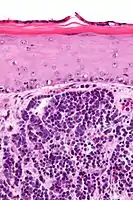

Diagnosis of MCC begins with a clinical examination of the skin and lymph nodes.[25] Following clinical exam, definitive diagnosis of Merkel cell carcinoma (MCC) requires examination of biopsy tissue to identify its histopathologic features.[3][25] An ideal biopsy specimen is either a punch biopsy or a full-thickness incisional biopsy of the skin including full-thickness dermis and subcutaneous fat. On light microscopy, MCC shows basaloid tumor nests with neuroendocrine features ("salt and pepper" chromatin, scarce cytoplasm, and brisk mitotic activity).[3][25] In addition to standard examination under light microscopy, immunohistochemistry (IHC) is also generally required to differentiate MCC from other morphologically similar tumors such as small cell lung cancer, the small cell variant of melanoma, various cutaneous leukemic/lymphoid neoplasms, and Ewing's sarcoma. Neuroendocrine molecular markers such as synaptophysin or chromogranin A are characteristic of MCC and other neuroendocrine tumors, while other markers such as PAX5 or cytokeratin 20 can distinguish MCC from these tumors.ref name=Kervarrec2019/>[4] Longitudinal imaging may also help in ruling out a diagnosis of metastatic small cell lung cancer. Once an MCC diagnosis is made, a sentinel lymph node biopsy as well as other imaging is recommended as a part of the staging work-up needed to determine prognosis and subsequent treatment options.[3][25]

Merkel-cell carcinoma. Gross pathology specimen Micrograph of a Merkel-cell carcinoma. H&E stain

Micrograph of a Merkel-cell carcinoma. H&E stain Merkel-cell carcinoma (arrow) infiltrating skin tissue, stained brown for Merkel cell polyomavirus large T protein

Merkel-cell carcinoma (arrow) infiltrating skin tissue, stained brown for Merkel cell polyomavirus large T protein